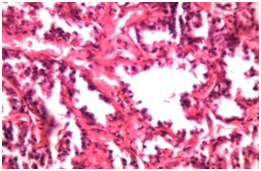

Figure 1 HP of Mammary adenocarcinoma showing ducts partially occluded with in growth of tumour cells and presence of extensive fibrous stroma.

Figure 2 HP of Mammary adenocarcinoma (pappilary form) showing papillary projections in the acinar lumen with pleomorphic and anaplastic cells and presence of mitotic figures.